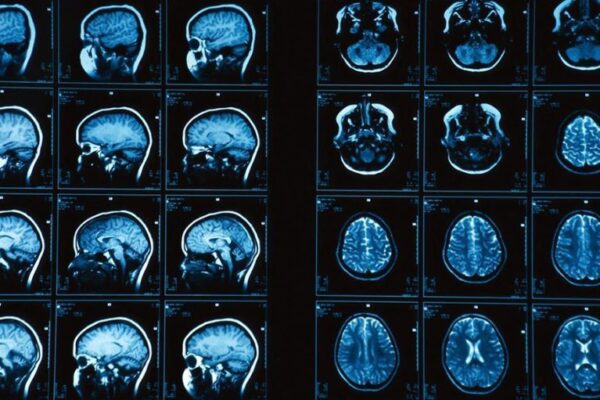

- 1.5 Tesla Emar

- Emar

- MR Spektroskopi